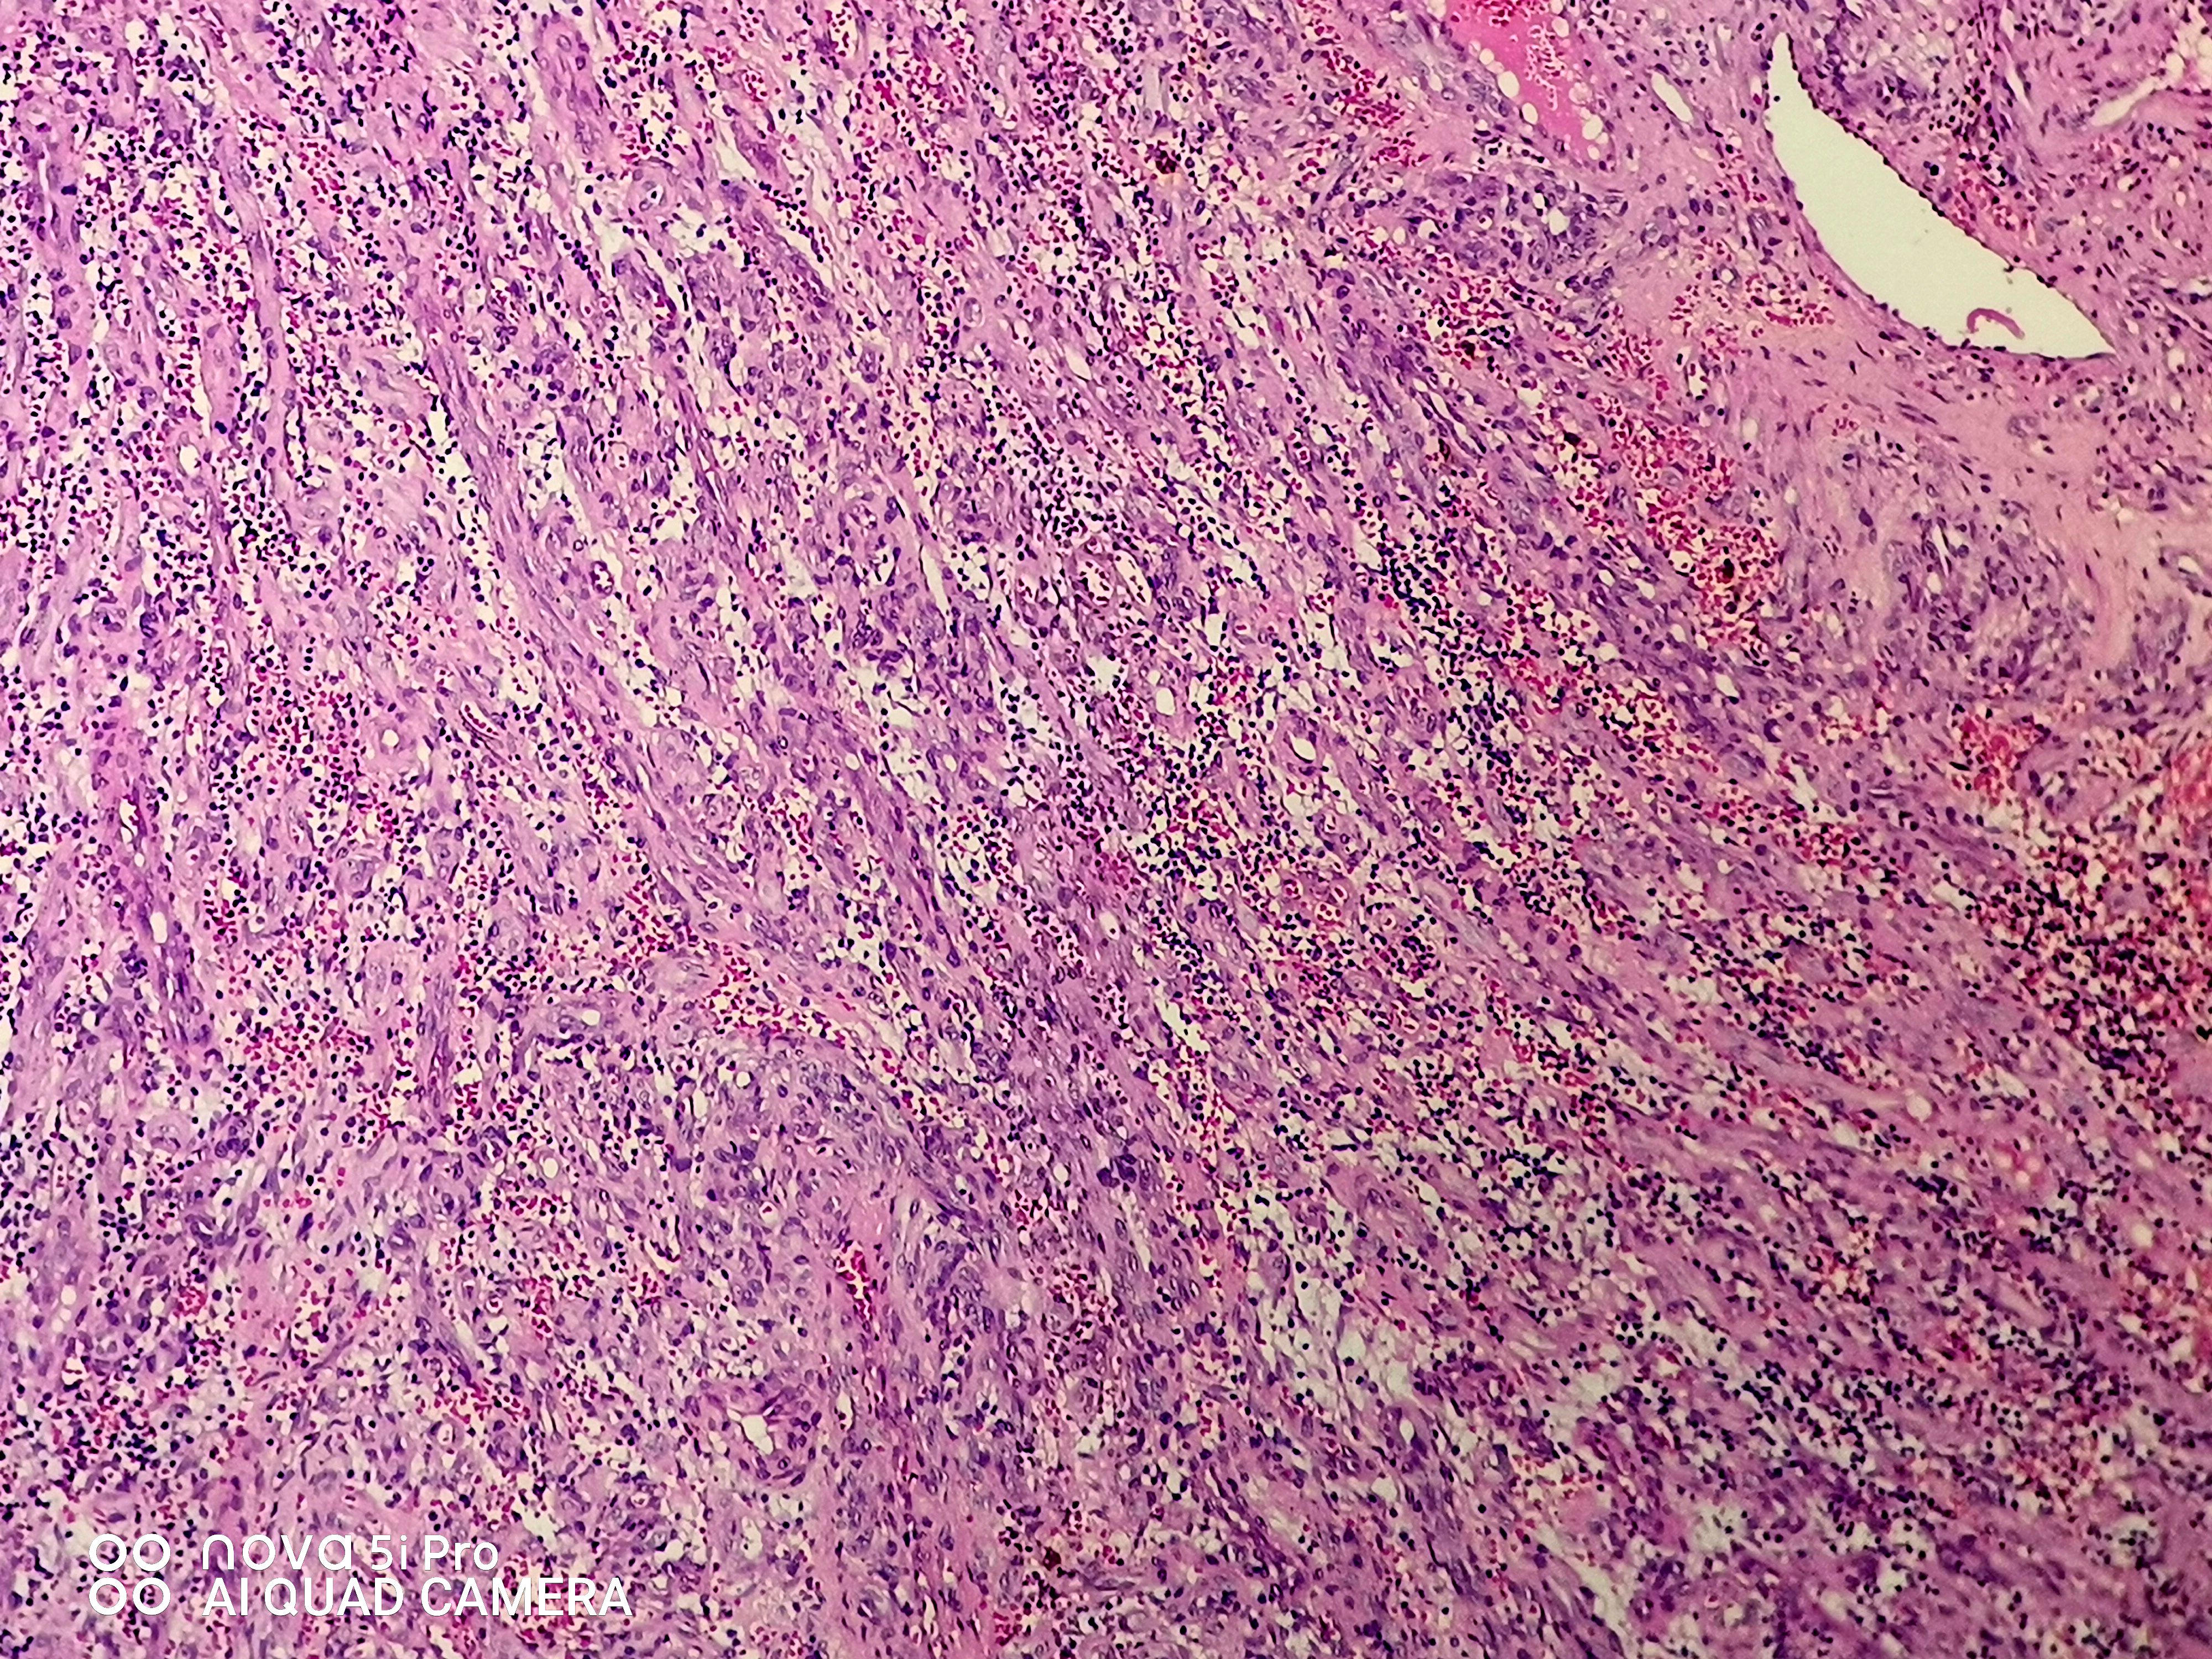

请老师们看看这个足跟肿块,血管瘤?谢谢了!

性别

女

年龄

43岁

临床诊断

待查

一般病史

发现左足跟肿块一年余

标本名称

左足跟肿块

大体所见

组织一块,大小约1.6*1.0*0.6cm,切开,实性灰白夹褐质中,一盒全取。

肉芽肿性毛细血管瘤。